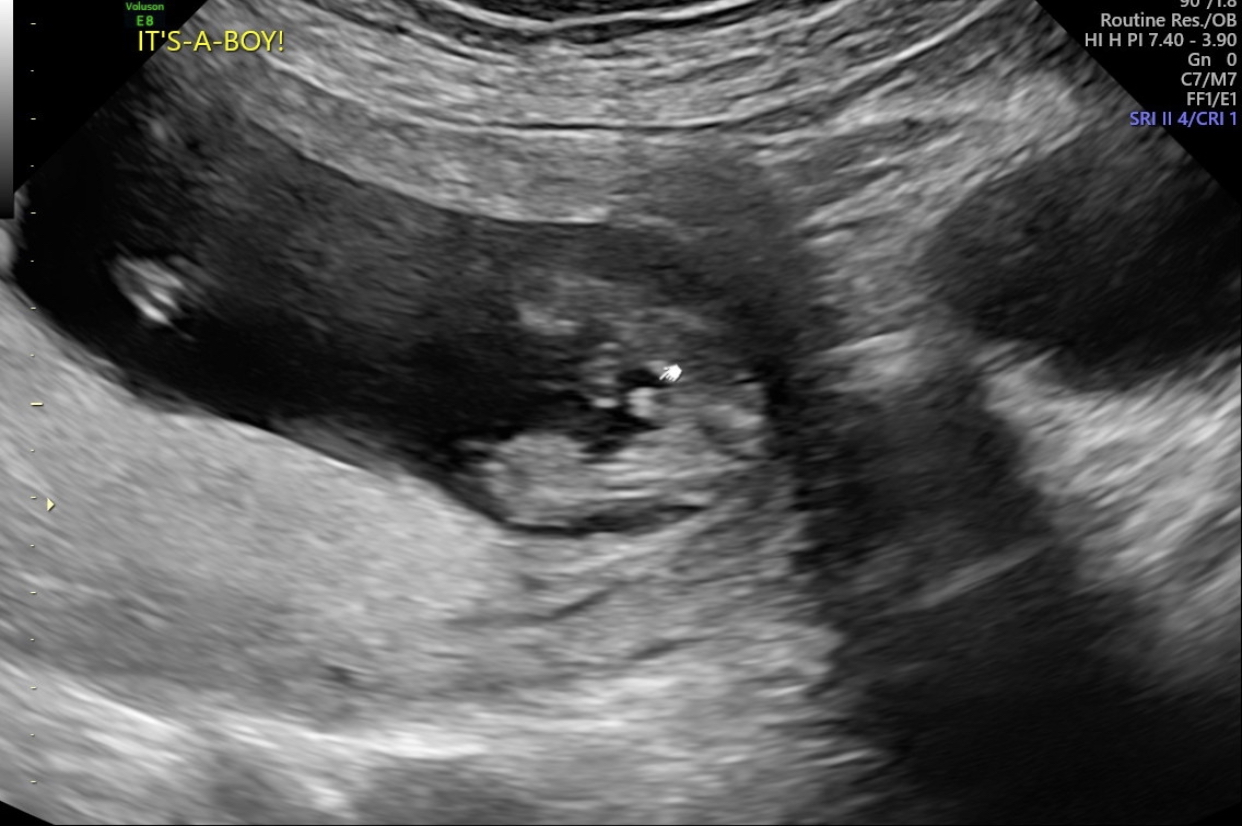

Had my midwife appointment today at 14+ weeks. She had a hard time getting and keeping baby on the Doppler so we couldn’t really hear baby’s heart beat. Obviously I was terrified thinking all of the thoughts but luckily the ultrasound person was able to fit me in between appointments. I got to see baby and she was able to confirm that baby DID have a beat. On top of that she was able to confirm that baby was indeed a HE!! Legs were crossed but she got a pretty good potty shot. So thankful for the HEALTHY baby boy!! :DS::DS:

Attachment 43608